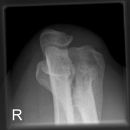

Ellenbogen seitlich nach N. Stjepanovic

Aufgrund der Winkelung von 10° bzw 15° erscheinen paar Strukturen verkürzt.

Qualitätskriterien

Durch diese exakte Einstellung von N. Stjepanovic ist das humero-ulnar-Gelenk sehr gut einsehbar.